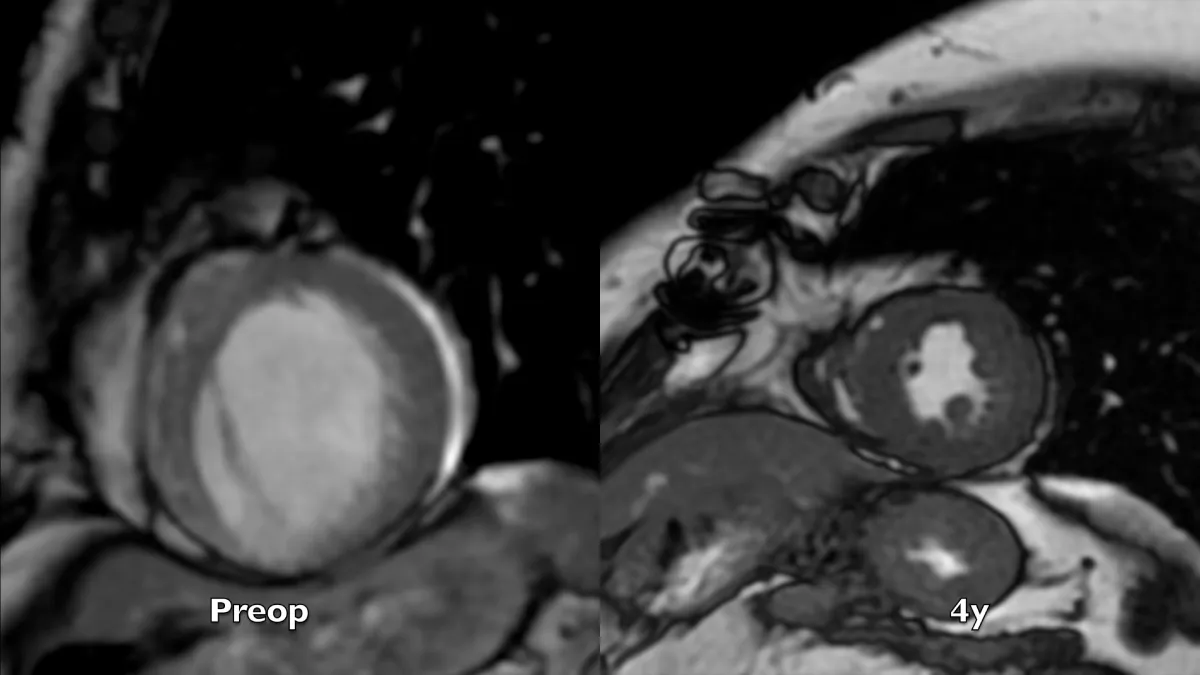

Figure 2: Magnetic resonance long axis systolic frames at two controls, preoperative and 4 years after the operation. A near-normal chamber geometry and wall thickening is evident. Note the reduction of left atrial volume, even in the absence of preoperative mitral regurgitation.

Figure 3: Magnetic resonance short axis systolic frames at two controls, preoperative and 4 years after the operation. The whole left ventricular chamber is restored and the remote myocardium regains its mechanics.

Preoperative imaging shows a very large dyskinetic region equal to around half of the ventricular chamber, conditioning a box-shaped ventricle with severely impaired global contraction, wall thickening, and diastolic function. Surgical reconstruction achieved an elliptic chamber with a normal volume and a new apex that were maintained along the years, gradually improving global ejection fraction and diastolic indices (Table 1), showing a positive remodeling induced by the optimised geometrical and functional parameters, left ventricular torsion included. Remote regions show a renewed, increased thickening granted by the better chamber geometry and fibers’ realignment, and the whole left ventricle shows a time-dependent restoration of its functional reserve, preoperatively hidden by the unfavourable functional conditions.